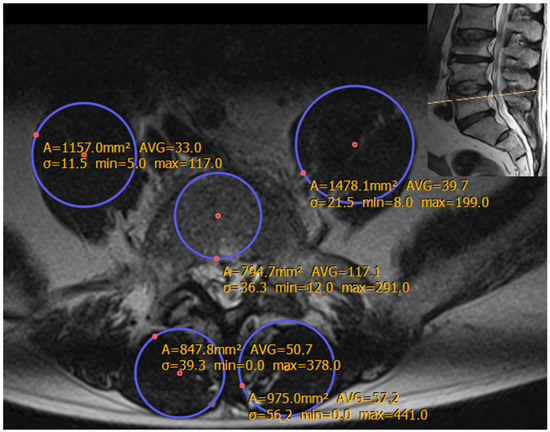

3.1. Sex-Specific Musculoskeletal Analysis (Table 3, Figure 2)